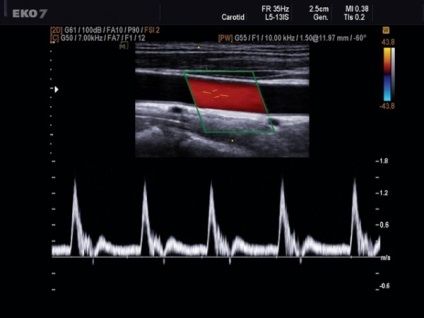

Szóval, mi is az a Doppler? A tanuló ebben a kérdésben, akkor egyértelmű, hogy ez a technika az ultrahang tanulmányozása az állam a véráramlást különböző hajók, mind a nagy és közepes méretű. Ellentétben az egyszerű ultrahangos módszer alkalmazásán alapuló úgynevezett Doppler-effektus. Mi olyan vonzó ez a módszer a vizsgálat?

Mi ő Doppler? Effect kültéri osztrák fizikus Doppler abban a tényben rejlik, hogy az ultrahang nyaláb visszaverődik a mozgó tárgyak, például a vérsejtek. Ennek eredményeként, a visszaverődést változó frekvenciája a kibocsátott jel, és ez lehetővé teszi, hogy értékelje nem csak a vér áramlási sebességének hanem az irányt a jelenlegi térfogat per perc, a jelenléte érelzáródás, lüktetés, az ateroszklerotikus stenosis. Segítségével által szolgáltatott adatok Doppler, meg tudjuk becsülni a kollaterális keringés.

Így a betegnél Doppler ultrahang. Milyen eredményeket lehet kapni? Ez attól függ, hogy mi vizsgáltuk. Az orvos által vezérelt egyes számok az artériák és vénák, összehasonlítva az adatokat azok a számok, amelyek jellemzője az egészséges arcot.

- Ez az arány a vér áramlását. Minden véna vagy artéria saját.

- A szisztolés-diasztolés paraméterek, azaz arány a legmagasabb és a legalacsonyabb a véráramlás sebességét.

- Pulzáció index, azaz az arány a különbség a vér áramlási sebesség az átlagos sebesség a vizsgált edények.

- rezisztencia index, ez ugyanaz - a különbség a sebességek szisztolé és diasztolé, osztva a szisztolés áramlási sebességének.

- A vastagsága az érfal. Jellemzően, ez változik 0,9 és 1,1 mm.